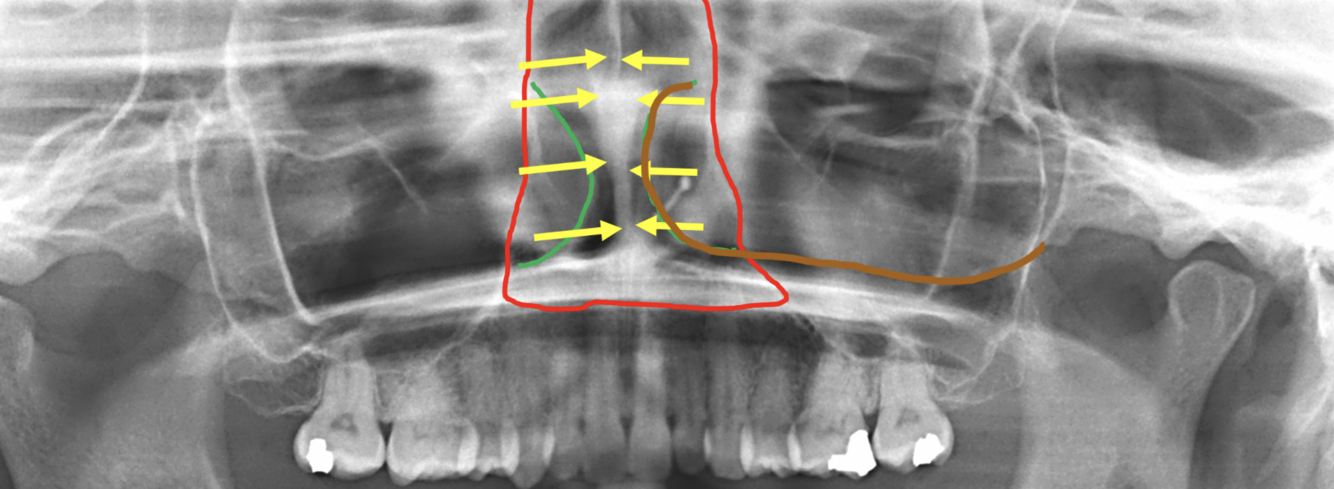

12

Q

Label the following image:

A

1. red: nasal cavity

2. green: conchae

3. yellow: nasal septum